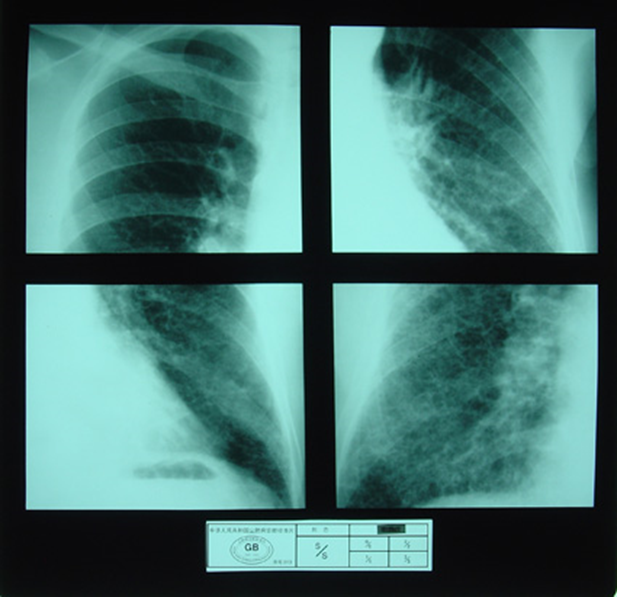

(2)X射线胸片表现:矽肺X射线胸片影像是肺组织矽肺病理形态在X射线胸片的反映,是“形”和“影”的关系,与肺内粉尘蓄积、肺组织纤维化的病变程度有一定相关关系,但由于多种原因的影响,并非完全一致。这种X射线胸片改变表现为X射线通过病变组织和正常组织对X射线吸收率的变化,呈现发“白”的圆形或不规则形小阴影,作为矽肺诊断依据。X射线胸片上其他影像,如肺门变化、肺气肿、肺纹理和胸膜变化,对矽肺诊断也有参考价值。在X射线胸片上,肺野内直径或宽度不超过10mm的阴影。小阴影按其形成分为圆形和不规则形两类。

2)不规则形小阴影:多为接触游离二氧化硅含量较低的粉尘所致,病理基础主要是肺间质纤维化。表现为粗细、长短、形态不一的致密阴影。阴影之间可互不相连,或杂乱无章的交织在一起,呈网状或蜂窝状;致密度多持久不变或缓慢增高。按其宽度可分为s(<1.5mm)、t(1.5~3.0mm)、u(3.0~10mm)三种类型。早期也多见于两肺中下区,弥漫分布,随病情进展而逐渐波及肺上区。

不规则形小阴影(s类小阴影)

不规则形小阴影(t类小阴影)

不规则形小阴影(u类小阴影)

尘肺贰期

尘肺壹期

尘肺贰期

尘肺叁期